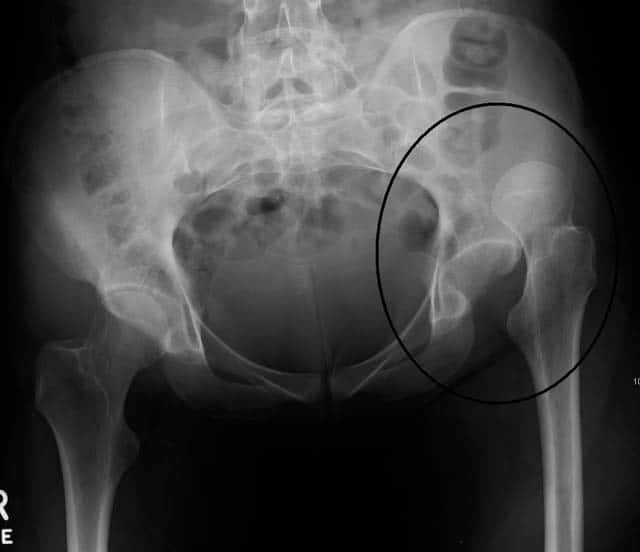

Fig 4 - Radiograph showing an anterior dislocation of the hip joint.

Fig 4

Radiograph showing dislocation of the left hip joint.